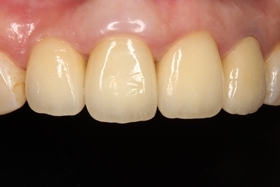

治療前,X光片及口內照片。

右上側門牙及左上正中門牙斷裂。